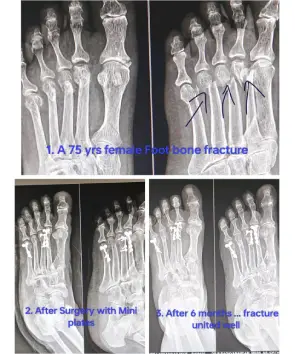

Dr. Keerthivasan Contact number WhatsApp